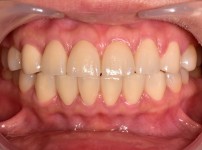

6

BEFORE

AFTER

클릭 해주세요.

전체교정

치아교정